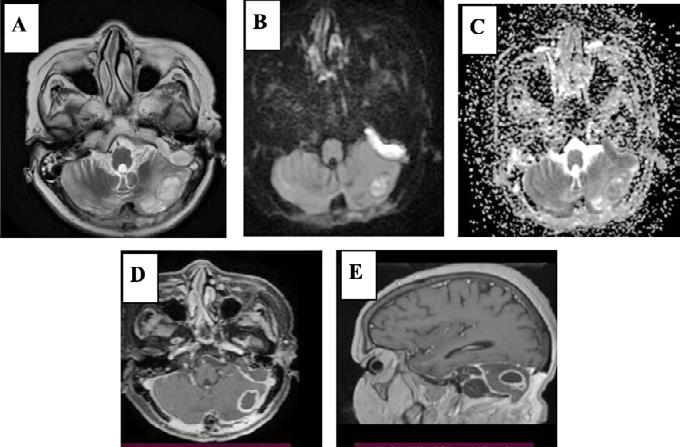

• Studiul opacifierii ramurilor corticale ale arterelor cerebrale medii (M4) drepte și stângi și a venelor cerebrale interne drepte și stângi (Fig.1).

Fig.1 ACTMS cranio-cerebrală, recon MIP în plan axial (a,b) și sagital (c): aspect normal; (a) opacifierea arterelor temporale dreaptă și stângă (săgeţi); (b) opaciferea ramurilor corticale ale arterelor cerebrale medii (M4)-săgeţi albe; opaciferea venelor cerebrale interne dreaptă și stângă (săgeţi negre-b și c).

Semiologie:

▶ Absența opacifierii M4 = 1 punct

▶ Opacifierea M4 = 0 punct

▶ Absența opacifierii venei cerebrale interne = 1 punct

▶ Opacifierea venei cerebrale interne = 0 puncte

• Un scor egal sau mai mare de 3 confirmă stopul circulator intracerebral. In acest caz, concluzia examinării este: „stop circulator intracerebral” care vine în sprijinul diagnosticului clinic de moarte cerebrală sau aspect ACT compatibil cu moartea cerebrală

• În caz contrar, concluzia examinării este „absența opririi circulatiei intracerebrale”, situaţie în care diagnosticul clinic de MC nu este confirmat.

În cazul opacifierii unilaterale a uneia dintre cele două artere cerebrale medii, diagnosticul de MC poate fi afirmată dacă este absentă opacifierea venelor cerebrale interne (Fig,2).